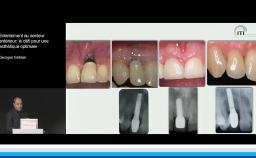

L’apport du flux tout numérique dans les extractions et implantation immédiate de l’unitaire à la réhabilitation bimaxillaire

Cette conférence décrit la mise en œuvre d’un flux numérique dans le but de contribuer au respect des principes biologiques qui régissent le succès implant-prothétique. Le positionnement tridimensionnel du ou des implants est l’élément clé d’une bonne intégration tissulaire et esthétique. La possibilité d’anticiper ce positionnement lors d’une planification numérique par rapport aux tissus osseux, aux tissus mous et au projet prothétique est une plus-value importante. Autre avantage, la mise en charge et la temporisation immédiate sont plus ergonomiques. La technique est déclinée pour les édentements unitaires, pluraux, et complets.